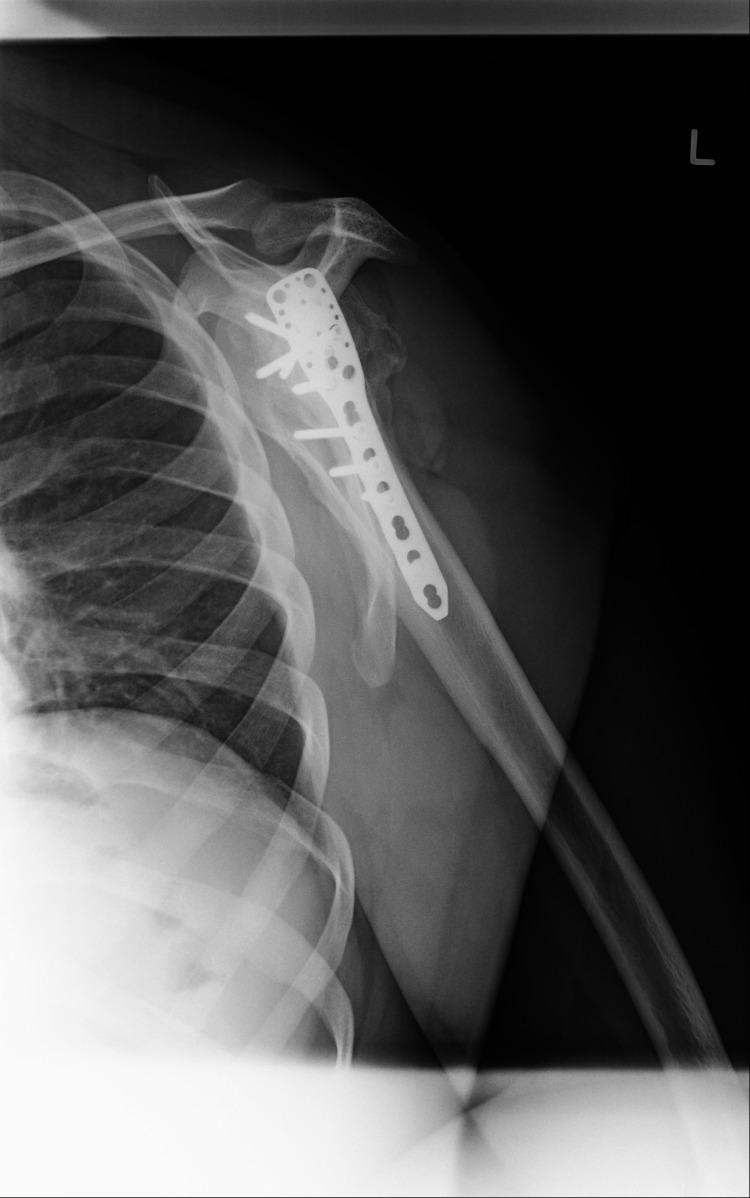

Bilateral shoulder dislocations are a rare occurrence and can be categorized as either symmetric (both humeral heads dislocate in the same direction) or asymmetric (wherein the humeral heads dislocate in different directions). Shoulder dislocations may be overlooked if they are the result of systemic injury; if diagnosed >21 days after occurring, they are considered chronic dislocations. We describe the case of a 31-year-old male who presented with an eight-week history of bilateral shoulder pain. His onset of pain coincided with a seizure secondary to Chikungunya encephalitis. Clinical and radiological examination demonstrated bilateral symmetric anterior shoulder dislocation with associated greater tuberosity fractures and extensive callus formation bilaterally. Open surgical management was performed first on the left shoulder via the deltopectoral approach. The callus was removed, the greater tuberosity fragment lifted off, reattached to the original position, and held in place with sutures and proximal humeral locking plates. The right shoulder was reduced six weeks after the left shoulder due to patient preference; the reduction utilized the same approach as with the left shoulder. Post-operatively the patient was immobilized, and physiotherapy commenced. He achieved a satisfactory range of motion four months post-operation. Physicians should be cognizant that shoulder pain after a convulsive seizure may signify shoulder dislocation. Thorough clinical and radiological examinations are warranted in such an instance. There exists no consensus on the treatment of chronic shoulder dislocations, but it is recommended that closed reduction only be attempted up to six weeks post-dislocation due to the high risk of iatrogenic fractures and neurovascular damage beyond this time.

双侧肩关节脱位较为罕见,可分为对称型(两个肱骨头向同一方向脱位)或不对称型(肱骨头向不同方向脱位)。如果双侧肩关节脱位是由全身损伤导致的,可能会被忽视;如果在脱位发生21天以后才被诊断出来,则被视为慢性脱位。我们报告一例31岁男性患者,其双侧肩部疼痛长达8周。他的疼痛发作与基孔肯雅热病毒性脑炎继发的癫痫发作同时出现。临床和影像学检查显示双侧肩关节对称前脱位,伴有大结节骨折及双侧广泛骨痂形成。首先通过胸大肌三角肌入路对左肩进行切开手术治疗。清除骨痂,将大结节骨块掀起,重新复位并固定到原始位置,用缝线和肱骨近端锁定钢板固定。由于患者的选择,右肩在左肩手术后6周进行复位;复位采用与左肩相同的方法。术后患者进行制动,并开始物理治疗。术后4个月,患者的活动范围恢复到令人满意的程度。医生应认识到惊厥性癫痫发作后的肩部疼痛可能意味着肩关节脱位。在这种情况下,有必要进行全面的临床和影像学检查。对于慢性肩关节脱位的治疗目前尚无共识,但由于脱位超过6周后进行手法复位会有较高的医源性骨折和神经血管损伤风险,因此建议仅在脱位后6周内尝试进行闭合复位。